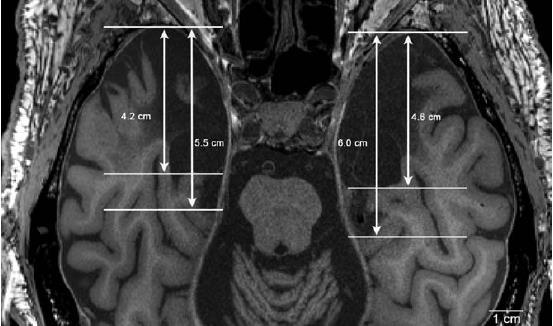

Las primeras resonancias magnéticas estructurales (RMNe)

se realizaron en 1992 (a los 66 años de edad) y 1993. La lesión dañó la mayor parte del complejo amigdaloide, la corteza entorrinal, parte de la corteza perirrinal, las porciones uncal y rostral del hipocampo y parte de la corteza parahipocampal.

Tomado

de Augustinack, J. C. et al., (2014). Hippocampus, 24, 1267-1286.

Izquierdo

Derecho

Tomado de Augustinack, J. C. et al., (2014). Hippocampus, 24, 1267-1286.

La mayor cantidad de territorio retirada el día de la operación fue la circunvolución parahipocampal, en particular las partes anteriores de la corteza perirrinal y la corteza entorrinal entera.

Como la resección de Scoville incluyó las cortezas peri-y entorrinal (origen) e hipocampo (fin) del circuito necesario para la memoria declarativa a largo plazo*, esta se volvió alterada.